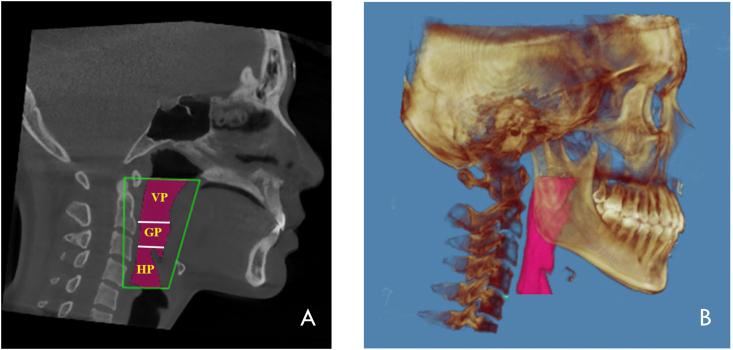

The 90 patients were collected to measure total pharyngeal airway volume (TP), velopharyngeal airway volume (VP), glossopharyngeal airway volume (GP), oropharyngeal airway volume (OP), hypopharyngeal airway volume (HP), and the smallest cross-sectional areas (SCA) of the upper respiratory tract as well as other relevant anatomical structures. The mean values differences between classes were analyzed using ANOVA. Pearson's test was used to compare classes in terms of the correlations between different factors.

Patients in skeletal classes I and III exhibited significantly higher SCA values (322.6 mmand 344.5 mm respectively) than those in skeletal class II (240.8 mm). Subjects from skeletal classes I and III exhibited significantly higher values of VP, HP, and OP than those in skeletal class II. Skeletal classes I and III exhibited significantly higher TP values (31190.1 mm and 30696.2 mm, respectively) than those in skeletal class II (22386.0 mm). Non-significant relationships were discovered between pharyngeal airway and skeletal pattern. Conversely, significant relationships were found between TP and gender, ANB, SNB, hyoid and pogonion positions.

The skeletal class II has smaller airway volume than those in skeletal class I and III. The pharyngeal airway volumes could serve as a guide in differentiating the different skeletal classes in clinical settings.